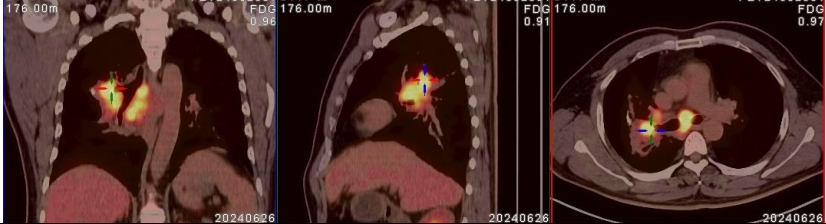

PET-CT进一步确诊,王先生为局部晚期肺癌。一家人又一次陷入了绝望……

治疗前

治疗后

两年过去了。最近一次复查胸部CT显示:原发病灶显著缩小,转移淋巴结持续消退。王先生恢复了正常生活,能走能跑,不再喘憋。